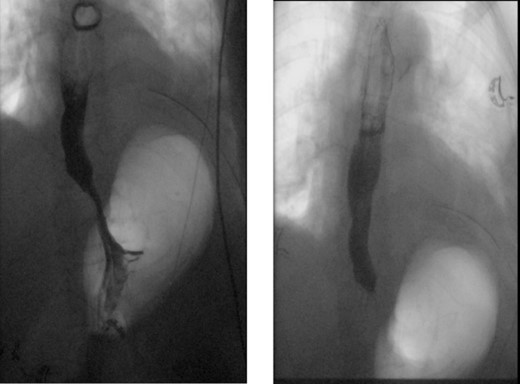

A 72-year-old woman with a past medical history of coronary artery disease and chronic gastroesophageal reflux disease (GERD) with hiatal hernia status postsurgical correction by Nissen’s fundoplication 20 years ago, presented with worsening episodes of intermittent dysphagia, heartburn, and postprandial cough of ~2 years duration but worsening symptoms over the past 2 months. She denies any symptoms of food regurgitation, nausea, vomiting, appetite, or weight changes. Upon her initial clinic evaluation, she had normal vital signs and unremarkable findings on the physical exam. The decision was made to start her empirically on a proton pump inhibitor, assuming her symptoms are related to GERD, to which she did not respond appropriately. A subsequent upper endoscopy revealed a large epiphrenic wide-mouthed ED (Fig. 1). Additionally, an esophagram showed a 6.0 × 5.0 cm epiphrenic ED with a 3.3 cm neck (Fig. 2). High-resolution esophageal manometry (HREM) was performed; thereafter, revealing a normal motility pattern (Fig. 3). She was then referred to cardiothoracic surgery for consideration of surgical repair. She was initially advised to follow a dysphagia-specific diet and wait conservatively on her symptoms, but no changes were observed in her clinical course over 6 months. The patient subsequently underwent a successful uncomplicated esophageal diverticulectomy with myotomy, conducted through a lateral thoracotomy. During surgery, an esophagogastroduodenoscopy (EGD) revealed an ED at 35 cm in the gastroesophageal (GE) junction at 40 cm in the epiphrenic region. A standard posterior lateral thoracotomy was performed in the serratus-sparing fashion, and the pleural space was entered at the seventh intercostal space. The esophagus was encircled with a Penrose drain lifting it up, and it was freed from the periaortic tissue, and the ED cleared off all muscle fibers. The diverticulum was excised from the esophagus using a purple load stapler with an EGD scope in place to prevent esophageal narrowing. A myotomy was performed from the GE junction proximally, with negative leak testing. The muscle layer was then imbricated over the area of diverticulectomy, and a chest tube was inserted for drainage. A postoperative esophagram confirmed no presence of an ED (Fig. 4). Immediately after the surgery, the patient had a complete resolution of her symptoms, and during her 1-year follow-up visit, she remained asymptomatic.

X-ray esophagram fluoroscopy showing a 6.0 × 5.0 cm epiphrenic ED with a 3.3 cm neck.

Normal X-ray esophagram fluoroscopy postdiverticulectomy with myotomy surgery.